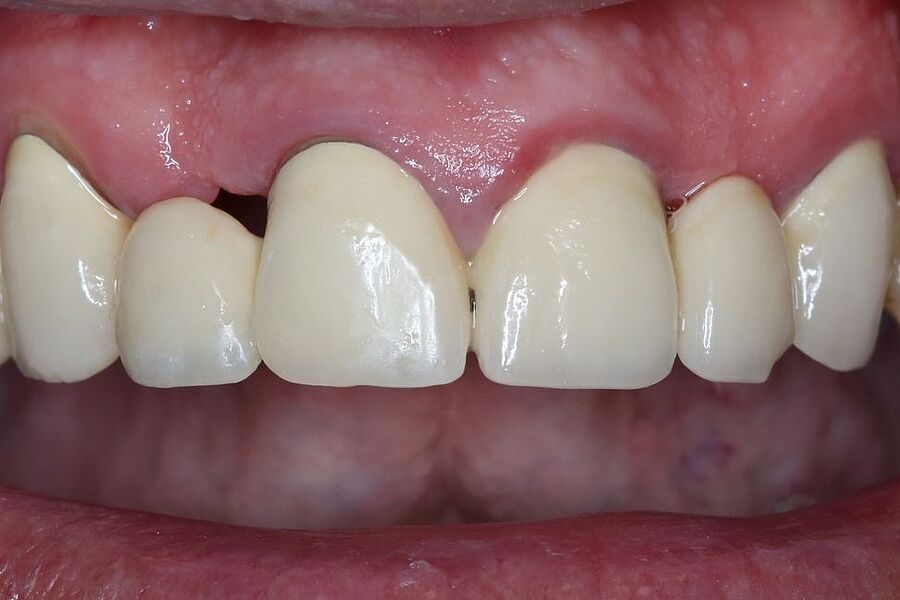

Eine neue Kasuistik zur Rehabilitation bei einer sehr komplexen Ausgangslage in der ästhetischen Zone ist in der Zeitschrift Implantologie des Quintessenz-Verlages erschienen. Als einzige deutschsprachige Zeitschrift aus dem zahnmedizinischen Bereich verfügt die Implantologie über einen kleinen Impact Factor. Konkret stellen die beteiligten Autoren in ihrem 13 Seiten umfassenden Case Report ein synoptisches Behandlungskonzept zur Rekonstruktion zu Verlust gegangener Hart- und Weichgewebe vor. Sie zeigen bei einer 31-jährigen Patientin die Umsetzung einer restaurativen Rehabilitation im anterioren Oberkiefer nach Zahnverlust und beidseitigen Nichtanlagen der seitlichen Schneidezähne.

Zeitschrift: Implantologie

Ausgabe: 02/2022, Seiten 203 – 215

Autoren: Dr. Eleftherios Grizas, Dr. Anna Gutbrodt, Dr. Julian Arnold, alle Dorow Clinic Lörrach, Dr. Dr. Hans Ulrich Brauer, M.A., M.Sc., Akademie für Zahnärztliche Fortbildung Karlsruhe